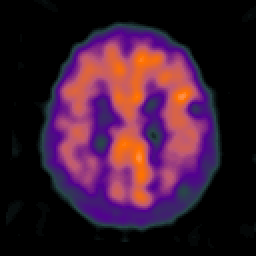

Alzheimer's disease: overlay -- Slice #18

[Home][Help][Clinical] Slice 18